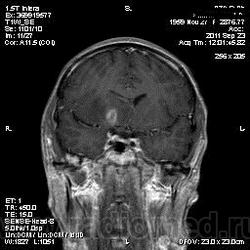

Похоже на метастазы

Тоже за метастазы. Достаточно большой отек при небольших образований.

я тоже думаю про метастазы, но уж сильно много сомнений.... и как будто бы капсула в субтенториальном очаге на нативных снимках, и на кт вроде бы как на абсцесс похоже.....

В данном случае был дифф. диагноз с абсцессом головного мозга (вариант сепсиса тоже рассматривался), т.к у пациента была и лихорадка и ЛОР-патология; но учитывая количество очагов (если смотреть все МР-снимки, выявляется ещё 2 мелких очага в коре) не исключено наличие метастазов + периферических характер накопления- можно предполагать и то и другое.

Это абсцессы. Равномерной толщины стенки, ровные контуры. На Т2 содержимое полостей имеет средний уровень сигнала - для абсцессов это характерно. Для дифференциации нужно было сделать DWI, тогда гной имел бы повышенный уровень сигнала. Хороший аппарат, почему не сделали?

Метастазы при отсутствующем онкоанамнезе в среднем возрасте бывают все же редко. К тому же лихорадка, лейкопения как проявление снижения иммунитета.

В левой теменной доле на границе с височной и затылочной вроде есть небольшая зона отёка (16 кадр из аксильной Т2 серии), не попавшая на постконтрастне снимки, что тут выложены,

выложила ДВИ, жаль не построить ИКД. Очаг на 16 срезе Т2 виден на постконтрастном срезе 3 в сагиттальной проекции; в коре теменной доли есть ещё два мелких очага, непопавших на данные снимки.

пришла положительная ф50 и ликвор с токсоплазмой

"мнрогоочаговое поражение головного мозга супра/субтенториальной локализации. Дифференциальный диагноз с инфекционным, метастатическим поражением головного мозга"